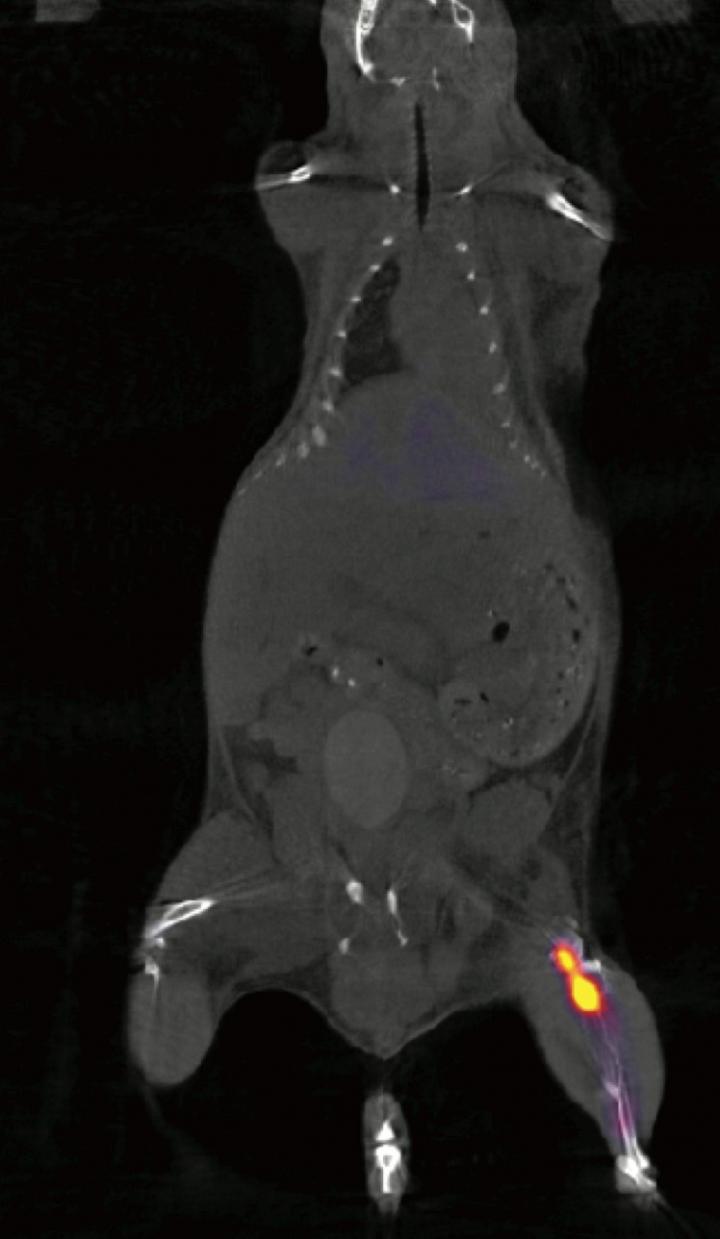

In the next phase of their experiments, the team made 11B6 "light up" during PET and fluorescence imaging by binding it to zirconium-89, creating a traceable radiochemical compound called 89Zr-11B6.

By imaging the 89Zr-11B6 using PET, the team showed that binding 11B6 to hK2 can measure activity of cancerous lesions robustly, in both soft tissue and bone. Prostate and breast cancer often metastasize to bone, therefore detection of lesions in all areas of the body is critical.

To further demonstrate the potential value of 89Zr-11B6 imaging, the team tested the imaging agent in disease models under standard treatment regimens. In one such case, disease activity was imaged and quantified in mice treated with saline and a second group with enzalutamide, a drug used to treat prostate cancer by inhibiting the androgen receptor hormone activity. All of the mice had prostate cancer.

Following initial castration, imaging of 89Zr-11B6 allowed the research team to see lower androgen receptor pathway activity, as one might expect. This effect was augmented in the animals with adjuvant enzalutamide treatment. This may inform current clinical practice as the use of adjuvant enzalutamide after castration may show benefit to patients with prostate cancer.